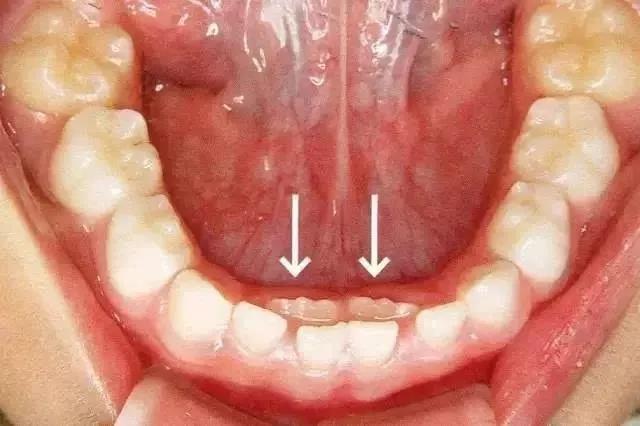

继承恒牙已萌出,乳牙未脱落(箭头指示继承恒牙)